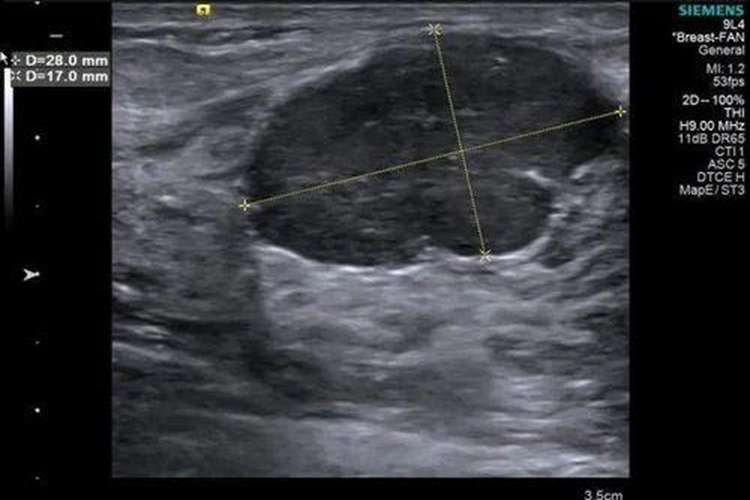

乳腺血管瘤:血管瘤一般位于皮下,表现为乳腺体表稍隆起的圆形肿块,大小不一,最大径可达8cm。边界不甚清楚,瘤组织软,状如海绵有压缩性,表面皮肤正常。若肿瘤位置浅表,可透过皮肤看到蓝色或青紫色肿瘤团块。超声检查表现为无回声或低回声影,X线检查可见圆形或分叶状高密度肿块影,可有钙化。